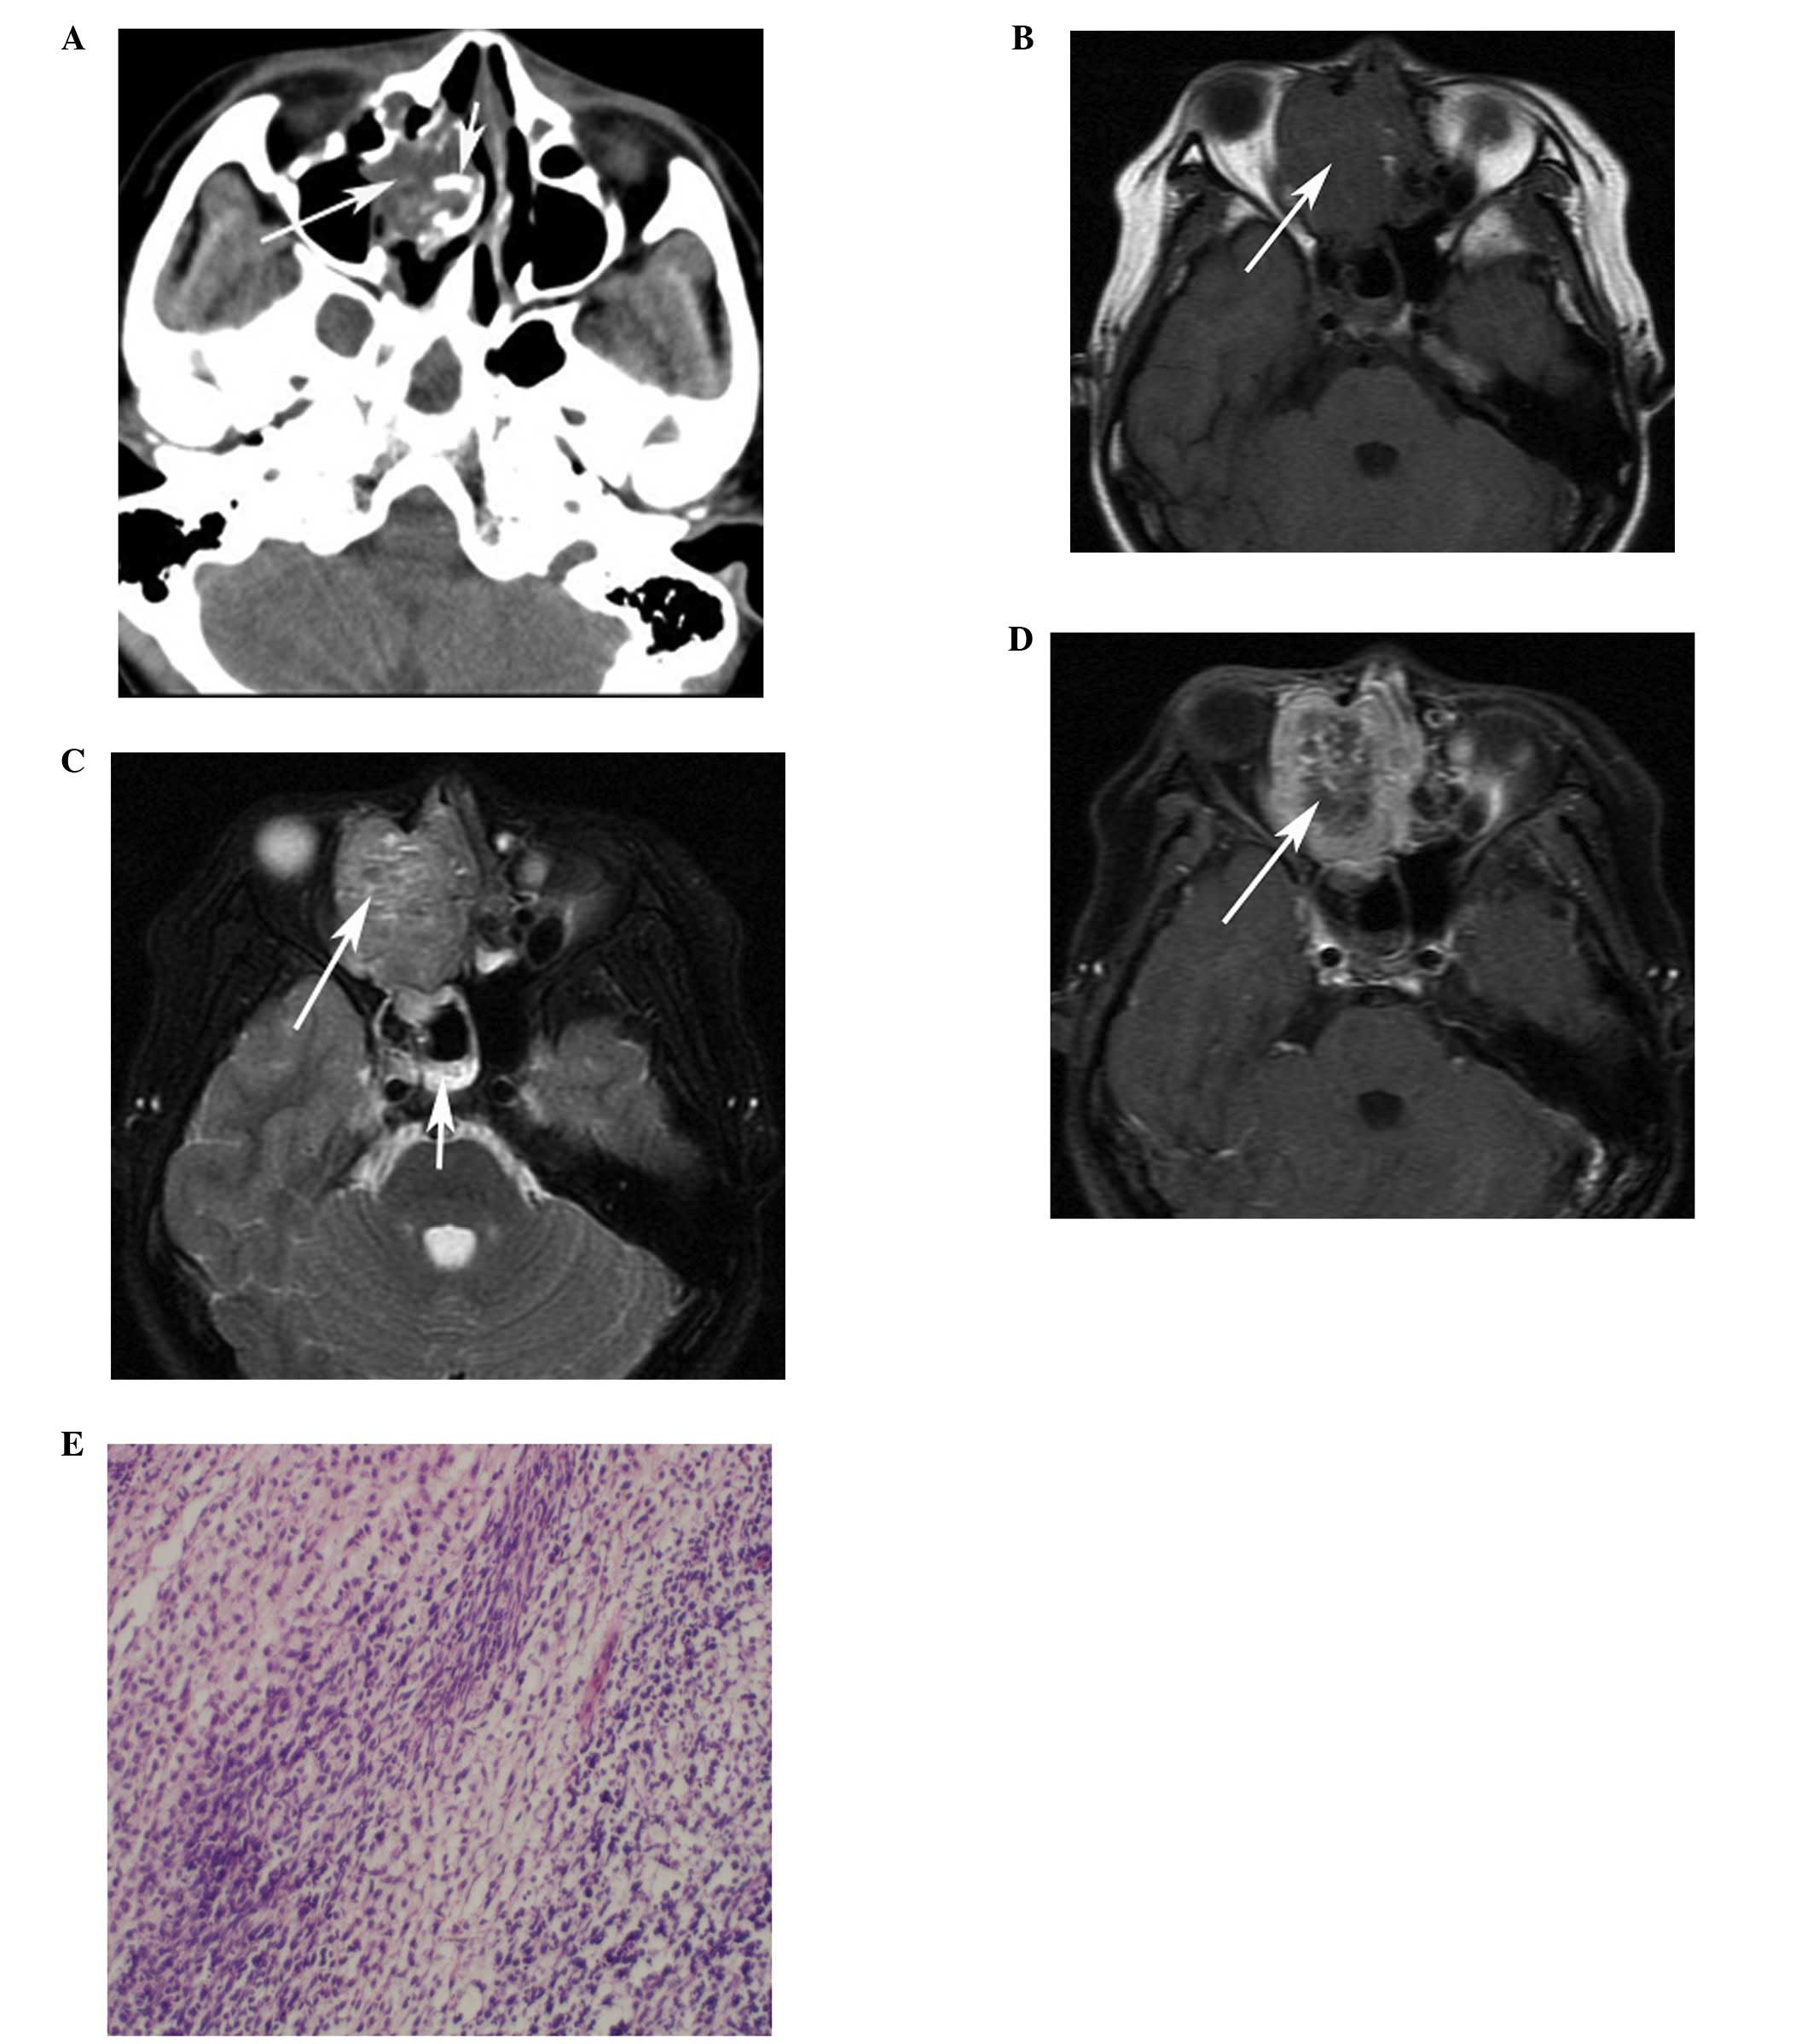

Computed Tomography And Magnetic Resonance Imaging Observations Of

www.spandidos-publications.com

www.spandidos-publications.com

rhabdomyosarcoma neck head embryonal axial tomography computed imaging magnetic observations resonance ol figure

Computed Tomography And Magnetic Resonance Imaging Observations Of

www.spandidos-publications.com

www.spandidos-publications.com

rhabdomyosarcoma computed tomography magnetic imaging observations resonance neck head figure ol